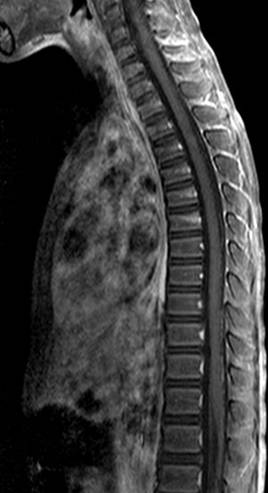

入院的当天,微侵袭神经外科的吴杰主任为阳阳完善了所有的检查及术前准备,并急诊实施了右侧脑室钻孔外引流术。术后阳阳复查,颅脑MRI提示:1、小脑蚓部占位性病变,考虑髓母细胞瘤可能性大(如图1);2、幕上梗阻性脑积水,并脑室周围间质性水肿(如图2);全脊髓MRI提示:胸腰段软脑膜线样高信号影,考虑肿瘤种植转移(如图3)。

图3,脊髓MR可见线样强化影,考虑脊髓种植转移;